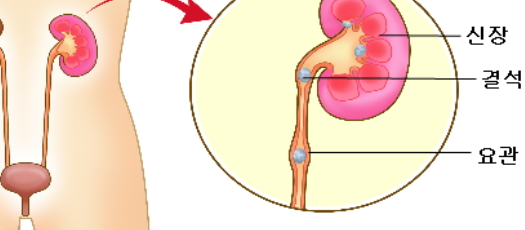

요로결석은 요도에 어떠한 원인으로 인해서 돌이 생김으로 소변을 보는데 문제가 생겨, 요도를 타고 움직이는 기관에 자극을 주어서 통증을 일으키는 질환입니다. 출산의 고통과 비슷하다는 통증을 일으키는 요로결석은 생각보다 많이 발생하는 질환으로 심해지면 신장의 기능을 손상시킬 수 있는 위험한 질환이기 때문에 각별히 주의하시는 것이 좋습니다.

요로결석 증상 중 대표적인 것은 바로 옆구리 통증입니다. 마치 칼로 찌르는 듯한 이 통증은 결석이 요관 즉, 콩팥의 콩팥 깔때기에 모아진 소변을 방광까지 운반해 주는 가늘고 긴 관에 있을 때 끼어있는 결석을 밀어내려고 심한 연동운동을 하게 되는데, 이 과정에서 호흡이 어려울 정도로 강한 통증으로 나타나게 됩니다.

요로결석 치료는 우선 진단을 한 후에 치료방법을 결정하게 되는데요. 진단은 옆구리 통증의 확인, 소변검사, 신장요관과 방광 부위를 촬영하는 검사, 신장, 요관, 방광의 모양과 기능을 동시에 보면서 진단, 엑스레이로 확인되지 않는 요석의 위치 확인을 위한 초음파 검사, CT촬영을 통해서 요로결석 진단을 하게 됩니다.